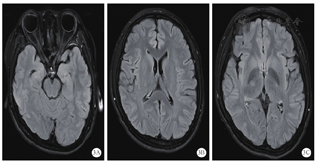

患者不能完全排除自身免疫性脑炎,转入ICU后,给予阿昔洛韦抗病毒、甘露醇脱水降颅压、乙酰谷酰胺营养脑细胞、静脉注射人免疫球蛋白和甲泼尼龙琥珀酸钠调节免疫、丙戊酸钠和左乙拉西坦控制癫痫等综合治疗。入院第4天,患者心率偏慢,最慢为40次/min左右,考虑存在自主神经功能紊乱,给予心宝丸及环磷腺苷葡胺提升心率;约4 d后心率逐渐恢复至75~120次/min,停用心宝丸和环磷腺苷葡胺。入ICU后仍间断出现癫痫发作,加用拉莫三嗪和苯巴比妥控制癫痫发作。入院第7天,患者血清及脑脊液自身免疫性脑炎相关抗体检测为阴性,脑脊液病原微生物基因组检测提示:猫立克次体感染(检出序列数261)。考虑患者存在立克次体感染可能,停用甲泼尼龙琥珀酸钠,给予盐酸米诺环素胶囊及甲磺酸左氧氟沙星氯化钠抗感染。入院第10天,患者间断出现呼吸暂停,伴有血氧饱和度下降,给予经口气管插管,呼吸机辅助呼吸。入院第12天,复查颅脑CT未见明显异常(图1A);胸部CT显示双肺多发高密度影,右肺上下叶部分支气管欠通畅,考虑感染性病变(图1B)。考虑患者肺部感染较重,给予头孢哌酮舒巴坦钠抗感染。入院第14天,复查脑脊液为无色清亮液体,压力约为217.6 mmH2O;脑脊液常规、蛋白未见明显异常。入院第15天和第16天,分别组织全院病例讨论及解放军总医院远程会诊,主要诊断考虑癫痫持续状态(难治性)、重症脑炎,脑炎性质考虑立克次体感染,不除外病毒感染,继续抗立克次体、抗病毒、丙种球蛋白抑制免疫反应、控制癫痫发作等治疗。入院第22天,第二次腰穿送检脑脊液病原微生物基因检测未再检测出猫立克次体。于当日复查颅脑CT显示双侧颞顶叶多发条片状稍低密度影,提示有脑炎可能(图1C);胸部CT显示双肺多发高密度影,右肺下叶部分支气管欠通畅,提示较前明显好转(图1D)。继续给予阿昔洛韦抗病毒,米诺环素及甲磺酸左氧氟沙星氯化钠抗立克次体治疗。入院第23天,拔除气管导管,患者呼吸平稳。入院第25天,患者出现皮疹,皮肤科会诊考虑:过敏性皮炎,重症多形性红斑?(药物引起可能性大)。给予甲泼尼松龙琥珀酸钠注射液60 mg静脉滴注,再次给予人免疫球蛋白0.4 g·kg-1·d-1静脉滴注,连用5 d。入院第27天起,患者的意识逐渐转清,可下床活动,能够配合指令完成动作,未再出现肢体抽搐。入院第32天,第3轮丙种球蛋白治疗结束,当日完善颅脑磁共振成像(magnetic resonance imaging,MRI)检查显示双侧额顶颞岛叶异常信号,考虑炎症,建议治疗后复查;右侧横窦、乙状窦较对侧纤细,考虑发育变异(图2)。入院第33天,患者转回普通病房,意识清,无头痛,无发热,颜面部及颈前皮疹较前减轻,四肢活动基本正常。入院第46天,患者好转出院,出院时意识清,问话对答切题,未见新发皮疹,四肢肌力5级,双侧巴宾斯基征阴性。出院4个月后,患者再次出现癫痫发作,复查颅脑MRI显示双侧额顶颞岛叶异常信号基本吸收、消失,脑部MRI增强未见异常强化(图3)。继续口服左乙拉西坦片,未再出现癫痫发作。